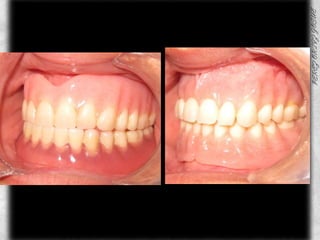

COMPARATIVOS

ANTECESDENTES PROSTODONTICOSPROSTODONCIA SUPERIOR CON 7 AÑOS DE USO Y DESGASTES EN TODOS LOS DIENTES, SIN PRESENCIA DE SARRO Y CON MOVILIDAD

PROSTODONCIA DEL PACIENTE INFERIORPROSTODONCIA INFERIOR CON BUENA ANATOMIA OCLUSAL EN LOS MOLARESCON 6 MESES DE USOBUEN SELLADO, SOLO SE HIZO LA INFERIOR

ANTERIOR DE PROSTODONCIADOS COLORES DIFERENTES DE ACRILICOSANTIESTETICA